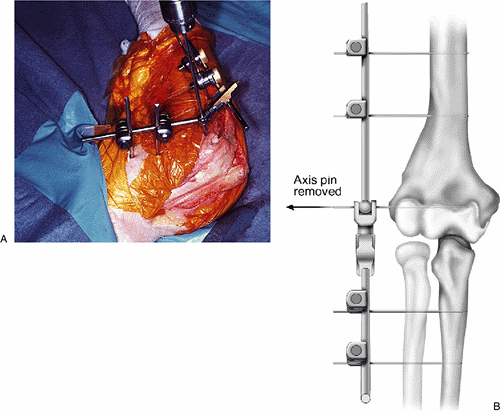

Figure 8-9. A,B:

Using the pin guide, a second half-pin is placed across the proximal

humerus distal to the first. If needed, a plus/minus 5 degrees of

out-of-plane rotation may be introduced to provide better target as

well as avoid soft-tissue injury (INSERT).

Figure 8-10. A distal ulna half-pin is applied with the use of the pin guide. Typically, the 3-mm guide is used.

Figure 8-11. After the distal pin has been coupled with the ulnar rod, a second pin is placed using the pin guide.